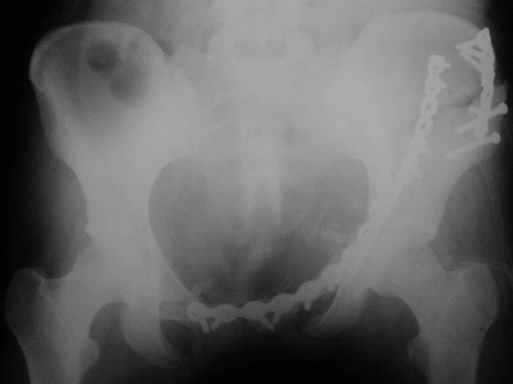

Рентгенограмма после операции. Изв. за качество. На днях переделаем.